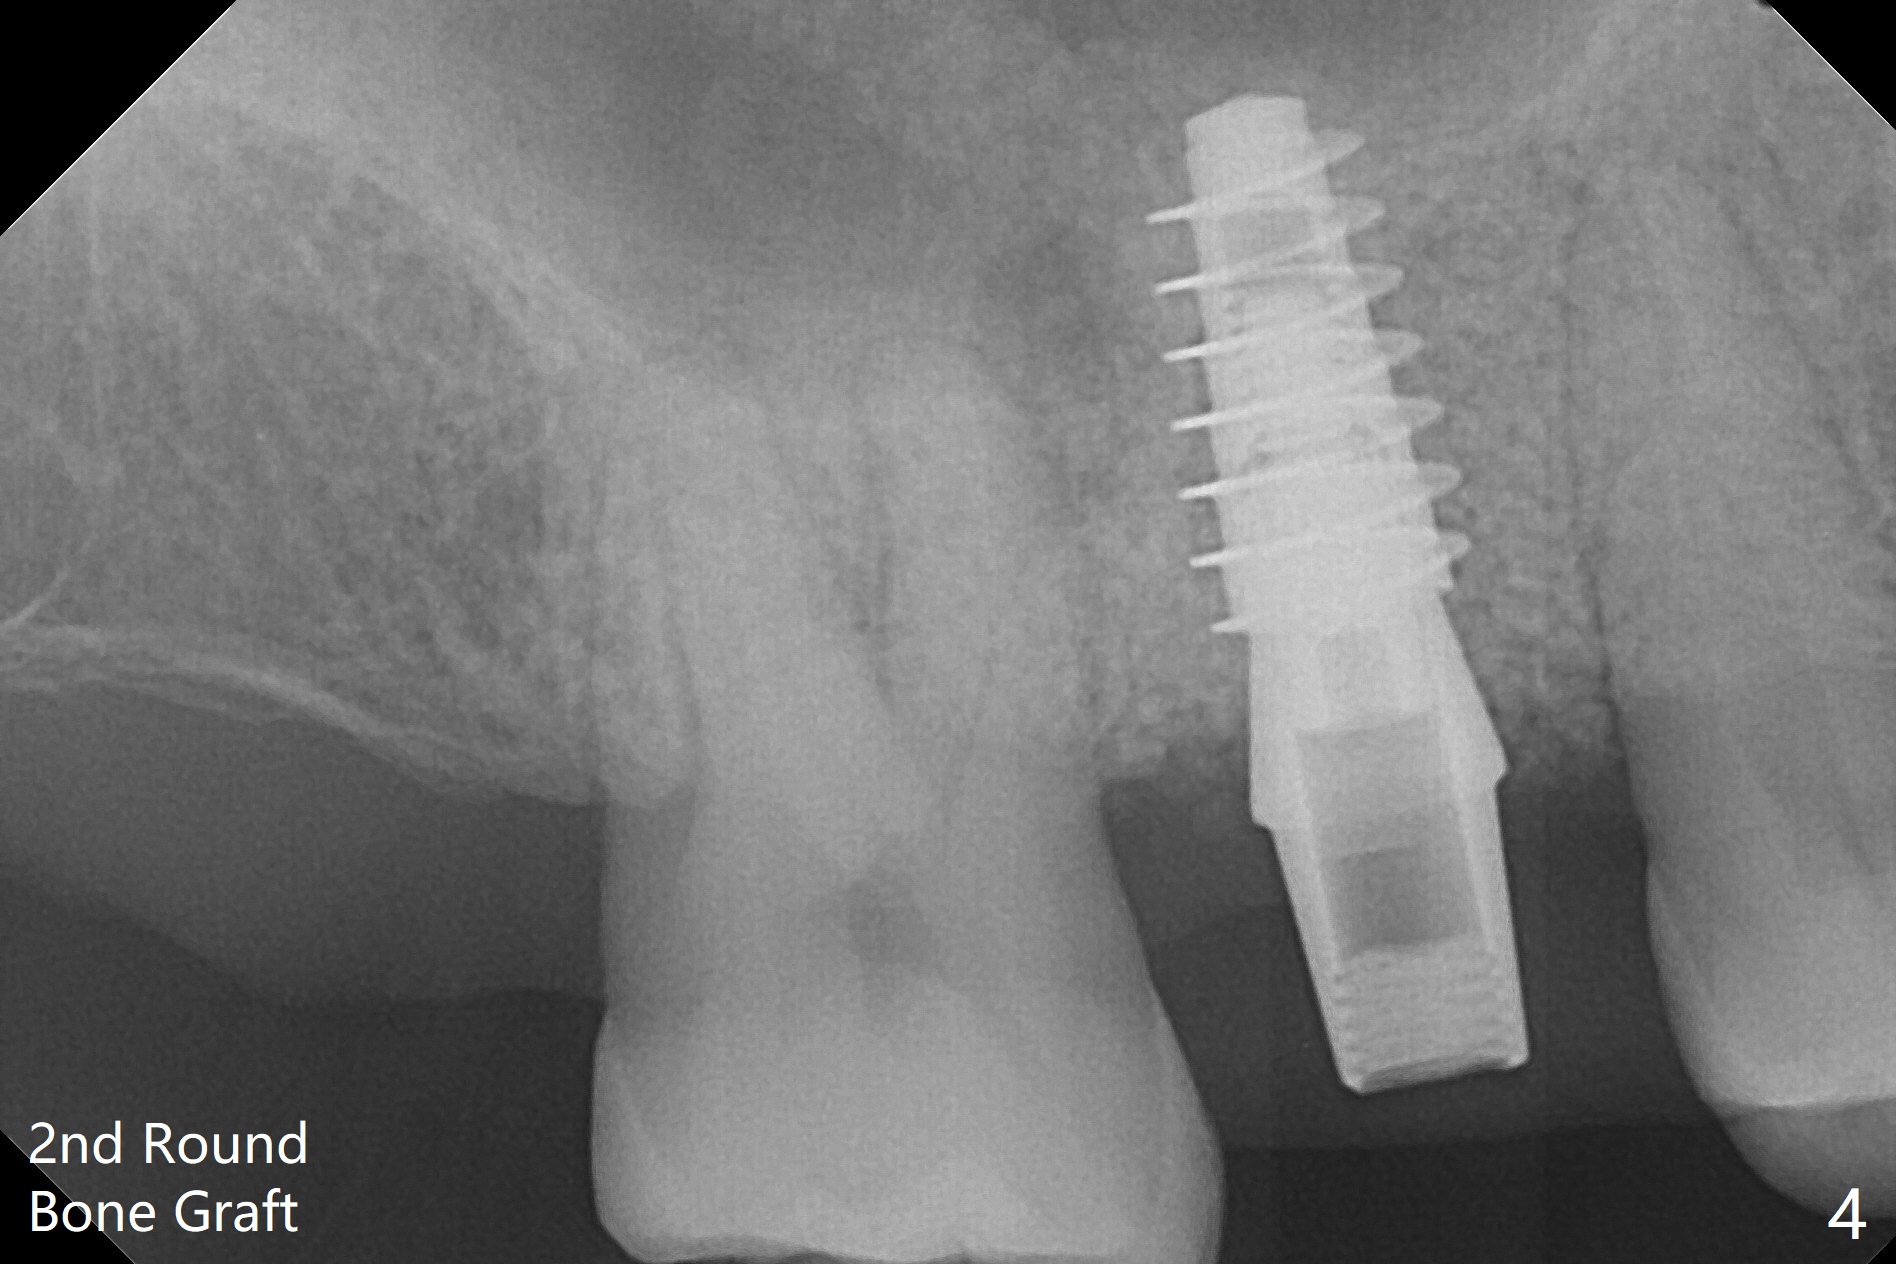

60岁男以前就害怕牙科治疗,一年前做一侧肾上腺切除,现在更紧张,不过挺配合。右上6手机切断拔除,虽然近中颊侧牙槽窝破坏厉害,中隔还很大(图一:S),利用导板顺利完成钻洞和提升术(图二:*)。植入正式植体后,放置第一轮粘性骨粉,至植体水平(确保植体深部周围没有缺失)而不影响基台置入,近中有不足之处(图三:*),第二轮骨粉补充(图四),最后覆盖PRF膜,临时牙冠固定。The crown/abutment/implant are found to have mild mobility 4.5 months postop, as related to #19 infection. A healing screw is placed. One month later, the wound heals; the bone density in the sinus increases (Fig.5 *), while that coronal to the implant decreases (^).愈合帽放置4个月,伤口还没有完全愈合,翻瓣后发现远中螺纹表面肉芽组织覆盖,去除后者,第一螺纹暴露。放置愈合基台后,从颊侧往远中缺陷填入骨粉(图六:*),缝合,覆盖树脂敷料。